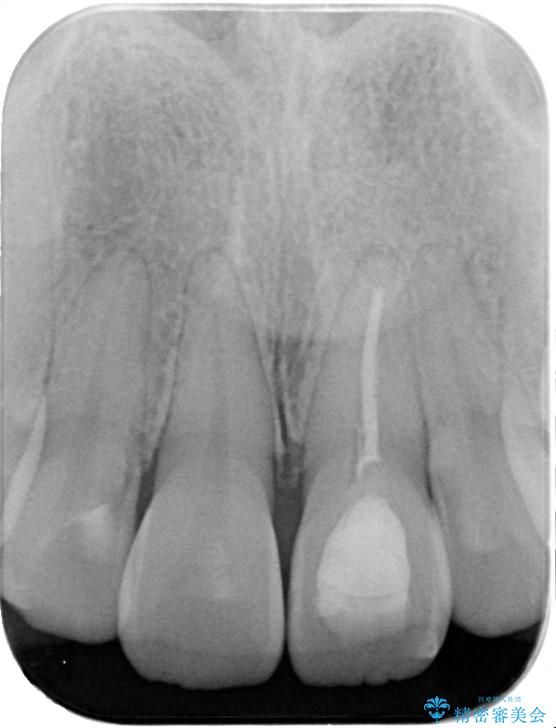

- 「以前、他院で神経を取った前歯がだんだん黒ずんできた」という見た目の改善を主訴にご来院されました。 診査の結果、神経を取り除いた後の歯(失活歯)特有の変色が起きており、さらに根の先端にわずかな影が見られたため、内部で感染が起きている可能性がありました。

精密な再根管治療: 古い充填材を除去し、歯科用顕微鏡を用いて根管内を徹底的に清掃・殺菌しました。根の先まで確実に薬剤を詰め直すことで、将来的な根尖病変(根の先の膿)のリスクを最小限に抑えました。